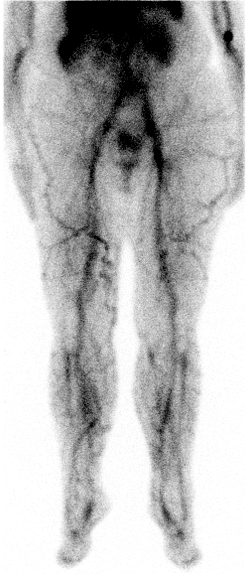

Radionuklidová flebografie je funkční zobrazovací metoda nukleární medicíny využívaná k hodnocení žilního návratu a průchodnosti hlubokého žilního systému dolních končetin a pánve.

Po intravenózní aplikaci radiofarmaka do žilního systému dolních končetin (obvykle dorzálně na noze) je sledována jeho dynamická distribuce proximálním směrem. Záznam umožňuje zhodnotit rychlost, symetrii a kontinuitu průtoku v jednotlivých segmentech.

- Normální nález: symetrický průchod radiofarmaka oběma DK bez známek obstrukce, rychlý transport do pánevních žil a duté žíly.

- Akutní HŽT: absence průtoku v úseku s trombózou, případně zástava postupu radiofarmaka.

- Chronická HŽT: zpomalený průtok, nepravidelná distribuce, přítomnost kolaterál.

- Kolaterální oběh: vizualizace náhradních žilních cest (paravertebrální, povrchové žíly DK).